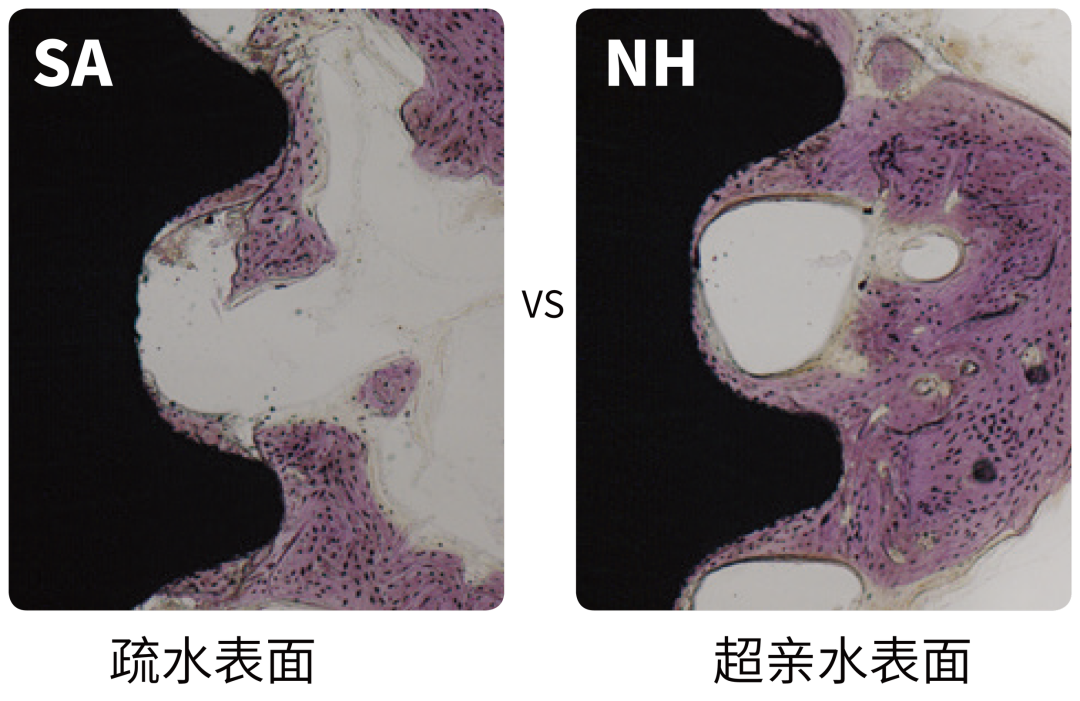

4. BIC显著改善

相比SA表面,超亲水生物可吸收磷灰石表面的BIC(骨-种植体接触)提升39%